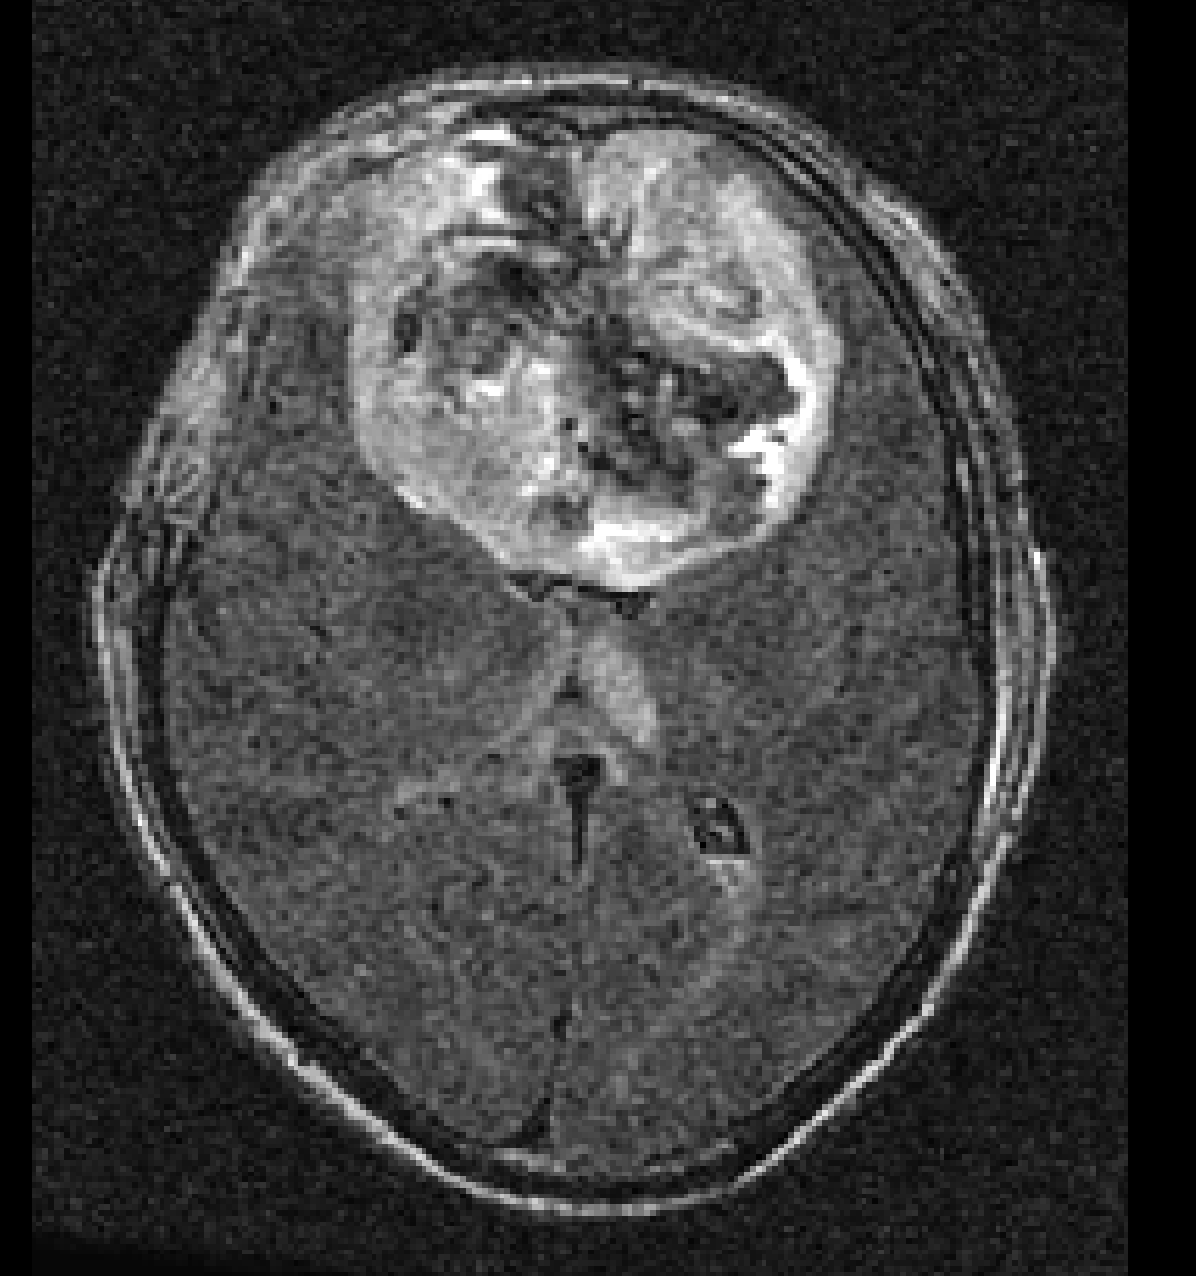

Finally, we considered two examples of scans that were incorrectly predicted by our method, see Figure 9. These two examples were chosen because our network assigned high prediction scores to the wrong classes for these cases. Figure 9(a) shows an example of a grade II, IDH mutated, 1p/19q co-deleted glioma that was predicted as grade IV, IDH wildtype by our method. Our method’s prediction was most likely caused by the hyperintensities in the post-contrast T1w scan being interpreted as contrast enhancement. Since these hyperintensities are also present in the pre-contrast T1w scan they are most likely calcifications, and the radiological appearance of this tumor is indicative of an oligodendroglioma. Figure 9(b) shows an example of a grade IV, IDH wildtype glioma that was predicted as a grade III, IDH mutated glioma by our method.